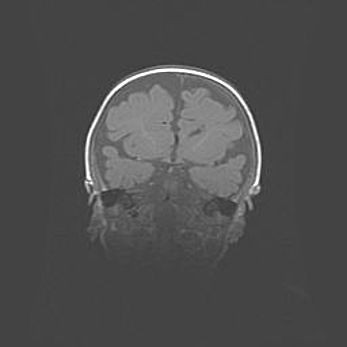

Аномалия Денди-Уокера. Признаки гипоплазии мозолистого тела.

Возраст: 5 месяцев 3 дня

Вес: 5550 г

Пол: мужской

Окружность головы: 39 см

Срок гестации: 40 недель

Аномалия Денди-Уокера – это порок развития головного мозга, для которого характерна триада симптомов: гипотрофия или аплазия червя мозжечка и/или полушарий мозжечка, расширение четвёртого желудочка с формированием ликворной кисты задней черепной ямки, гипертензионная гидроцефалия различной степени.

Гипоплазия мозолистого тела относится к дефектам внутриутробного этапа развития мозговой ткани, возникающим в процессе закладки структур головного мозга, что происходит на начальных этапах развития эмбриона.